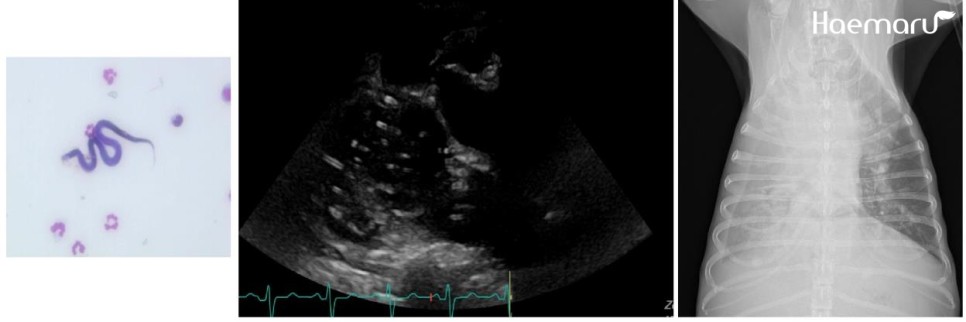

검사상 심장사상충 감염이 확인되며 사상충에 의한 폐고혈압이나 우심부전, 이로 인한 흉수 및 복수 발생이 의심되고 있습니다.

microfilaria, 우심내 심장사상반, 방사선상의 흉수소견